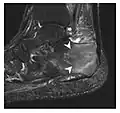

The greater tuberosity of the humerus is also an illustrative location of occult fractures. The osseous injury may follow seizures, glenohumeral dislocation, forced abduction, or direct impaction. They are commonly discovered on MRI in symptomatic patients with suspicion of rotator cuff tear. Coronal images are best suited for detection. They appear as crescentic oblique lines surrounded by a bone marrow edema pattern (Figure 5). The rotator cuff must be inspected since associated ligamentous lesions are common. In the ankle, malleoli and tarsal bones should be checked carefully for any cortical disruptions and radiolucent lines that may reveal a fracture. Awareness of the exact location of the pain will help direct the attention of the interpreter when searching for very subtle signs of fracture (Figure 6).[1]

a

b

Figure 6: Subtle anterior talar fracture in a 39-year-old man presenting with ankle pain after a fall. (a) Anteroposterior radiograph shows a subtle oblique radiolucent line through the talus (white arrows). (b) Sagittal CT reformation confirms the presence of an anterior talar fracture with cortical offset (black arrow). Avulsion fractures, which consist of a detached bone fragment resulting from a ligament or tendon pulling away from the bone, may also present with subtle radiographic signs. Tiny osseous fragments near the presumed attachment site of a ligament suggest this diagnosis. Common sites are the lateral tibial plateau (the Segond fracture), the spinal tuberosity of the tibia resulting from anterior cruciate ligament avulsion, and the ischial tuberosity.[1]

Figure 7: Fatigue fracture of the talus in a 25-year-old male basketball player with right hind foot and ankle pain, without history of trauma, and a normal initial radiograph (not shown). (a) One-month followup lateral radiograph shows normal appearance. (b) Sagittal T1-weighted MRI shows an irregular fracture line (arrow) within an ill-defined area of hypointensity corresponding to bone marrow edema.[1]